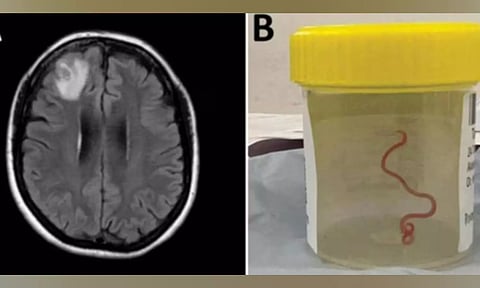

The Ophidascaris robertsi roundworm was pulled from the patient after brain surgery -- still alive and wriggling. It is suspected larvae, or juveniles, were also present in other organs in the woman’s body, including the lungs and liver.

"This is the first-ever human case of Ophidascaris to be described in the world," said Sanjaya Senanayake, leading ANU and Canberra Hospital infectious disease expert in a paper published in the journal Emerging infectious diseases.

"To our knowledge, this is also the first case to involve the brain of any mammalian species, human or otherwise. Normally the larvae from the roundworm are found in small mammals and marsupials, which are eaten by the python, allowing the life cycle to complete itself in the snake," Senanayake added.